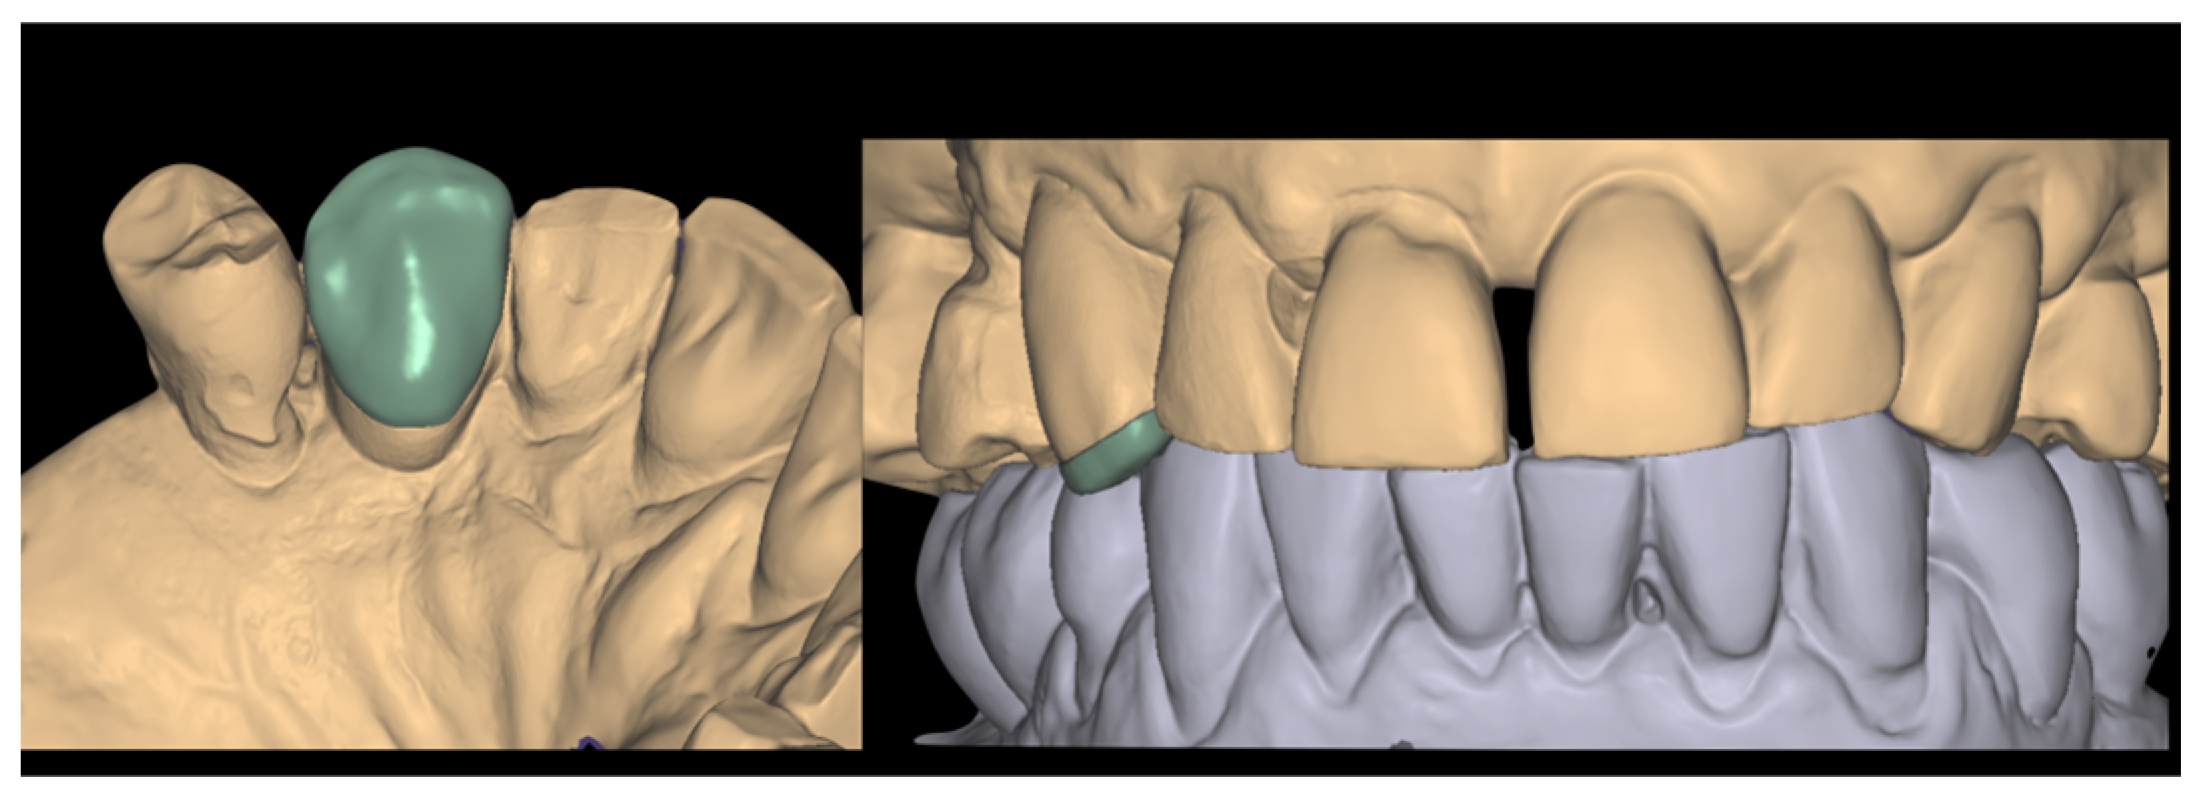

2.3. Laboratory Procedure

2.4. Crown Delivery